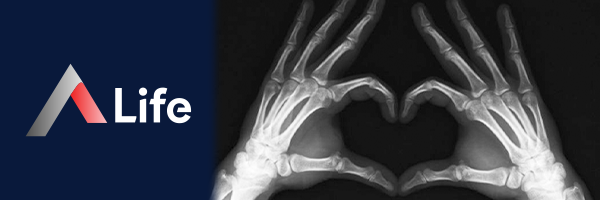

El Röntgeni​

El röntgeni, el kemiklerinin, eklemlerinin ve yumuşak dokularının ayrıntılı görüntülerini elde etmek için kullanılan yaygın bir tanısal görüntüleme yöntemidir. Bu işlemde, el bölgesinden X-ışınları geçirilir ve bu ışınlar özel bir film veya dijital dedektör üzerine düşürülerek el yapısının görüntüsü elde edilir. Röntgen, elde meydana gelen kırıklar, çıkıklar, kemik deformiteleri, artrit gibi eklem rahatsızlıkları ve diğer sorunların teşhisinde kullanılır.

El Röntgeni Ne İçin Kullanılır?

El röntgeni, birçok farklı amaç için kullanılabilir:

• Kırıklar: El kemiklerindeki kırıkları tespit etmek ve kırığın tipini ve yerini belirlemek.

• Çıkıklar: El eklemlerindeki çıkıkları teşhis etmek.

• Artrit: El eklemlerindeki kireçlenme (osteoartrit) veya diğer artrit türlerini değerlendirmek.

• Kemik deformiteleri: Doğuştan veya sonradan oluşan el kemiklerindeki şekil bozukluklarını teşhis etmek.

• Yabancı cisimler: Ele batmış olan yabancı cisimleri tespit etmek.

• Enfeksiyonlar: Kemik veya eklem enfeksiyonlarını değerlendirmek.

• Tümörler: El kemiklerindeki tümörleri teşhis etmek.

• El ağrısının nedenini belirlemek: El ağrısının nedenini anlamak için röntgen çekilebilir.

• Kemik yaşı tayini: Çocuklarda kemik gelişimini değerlendirmek ve kemik yaşını belirlemek için el röntgeni çekilebilir.